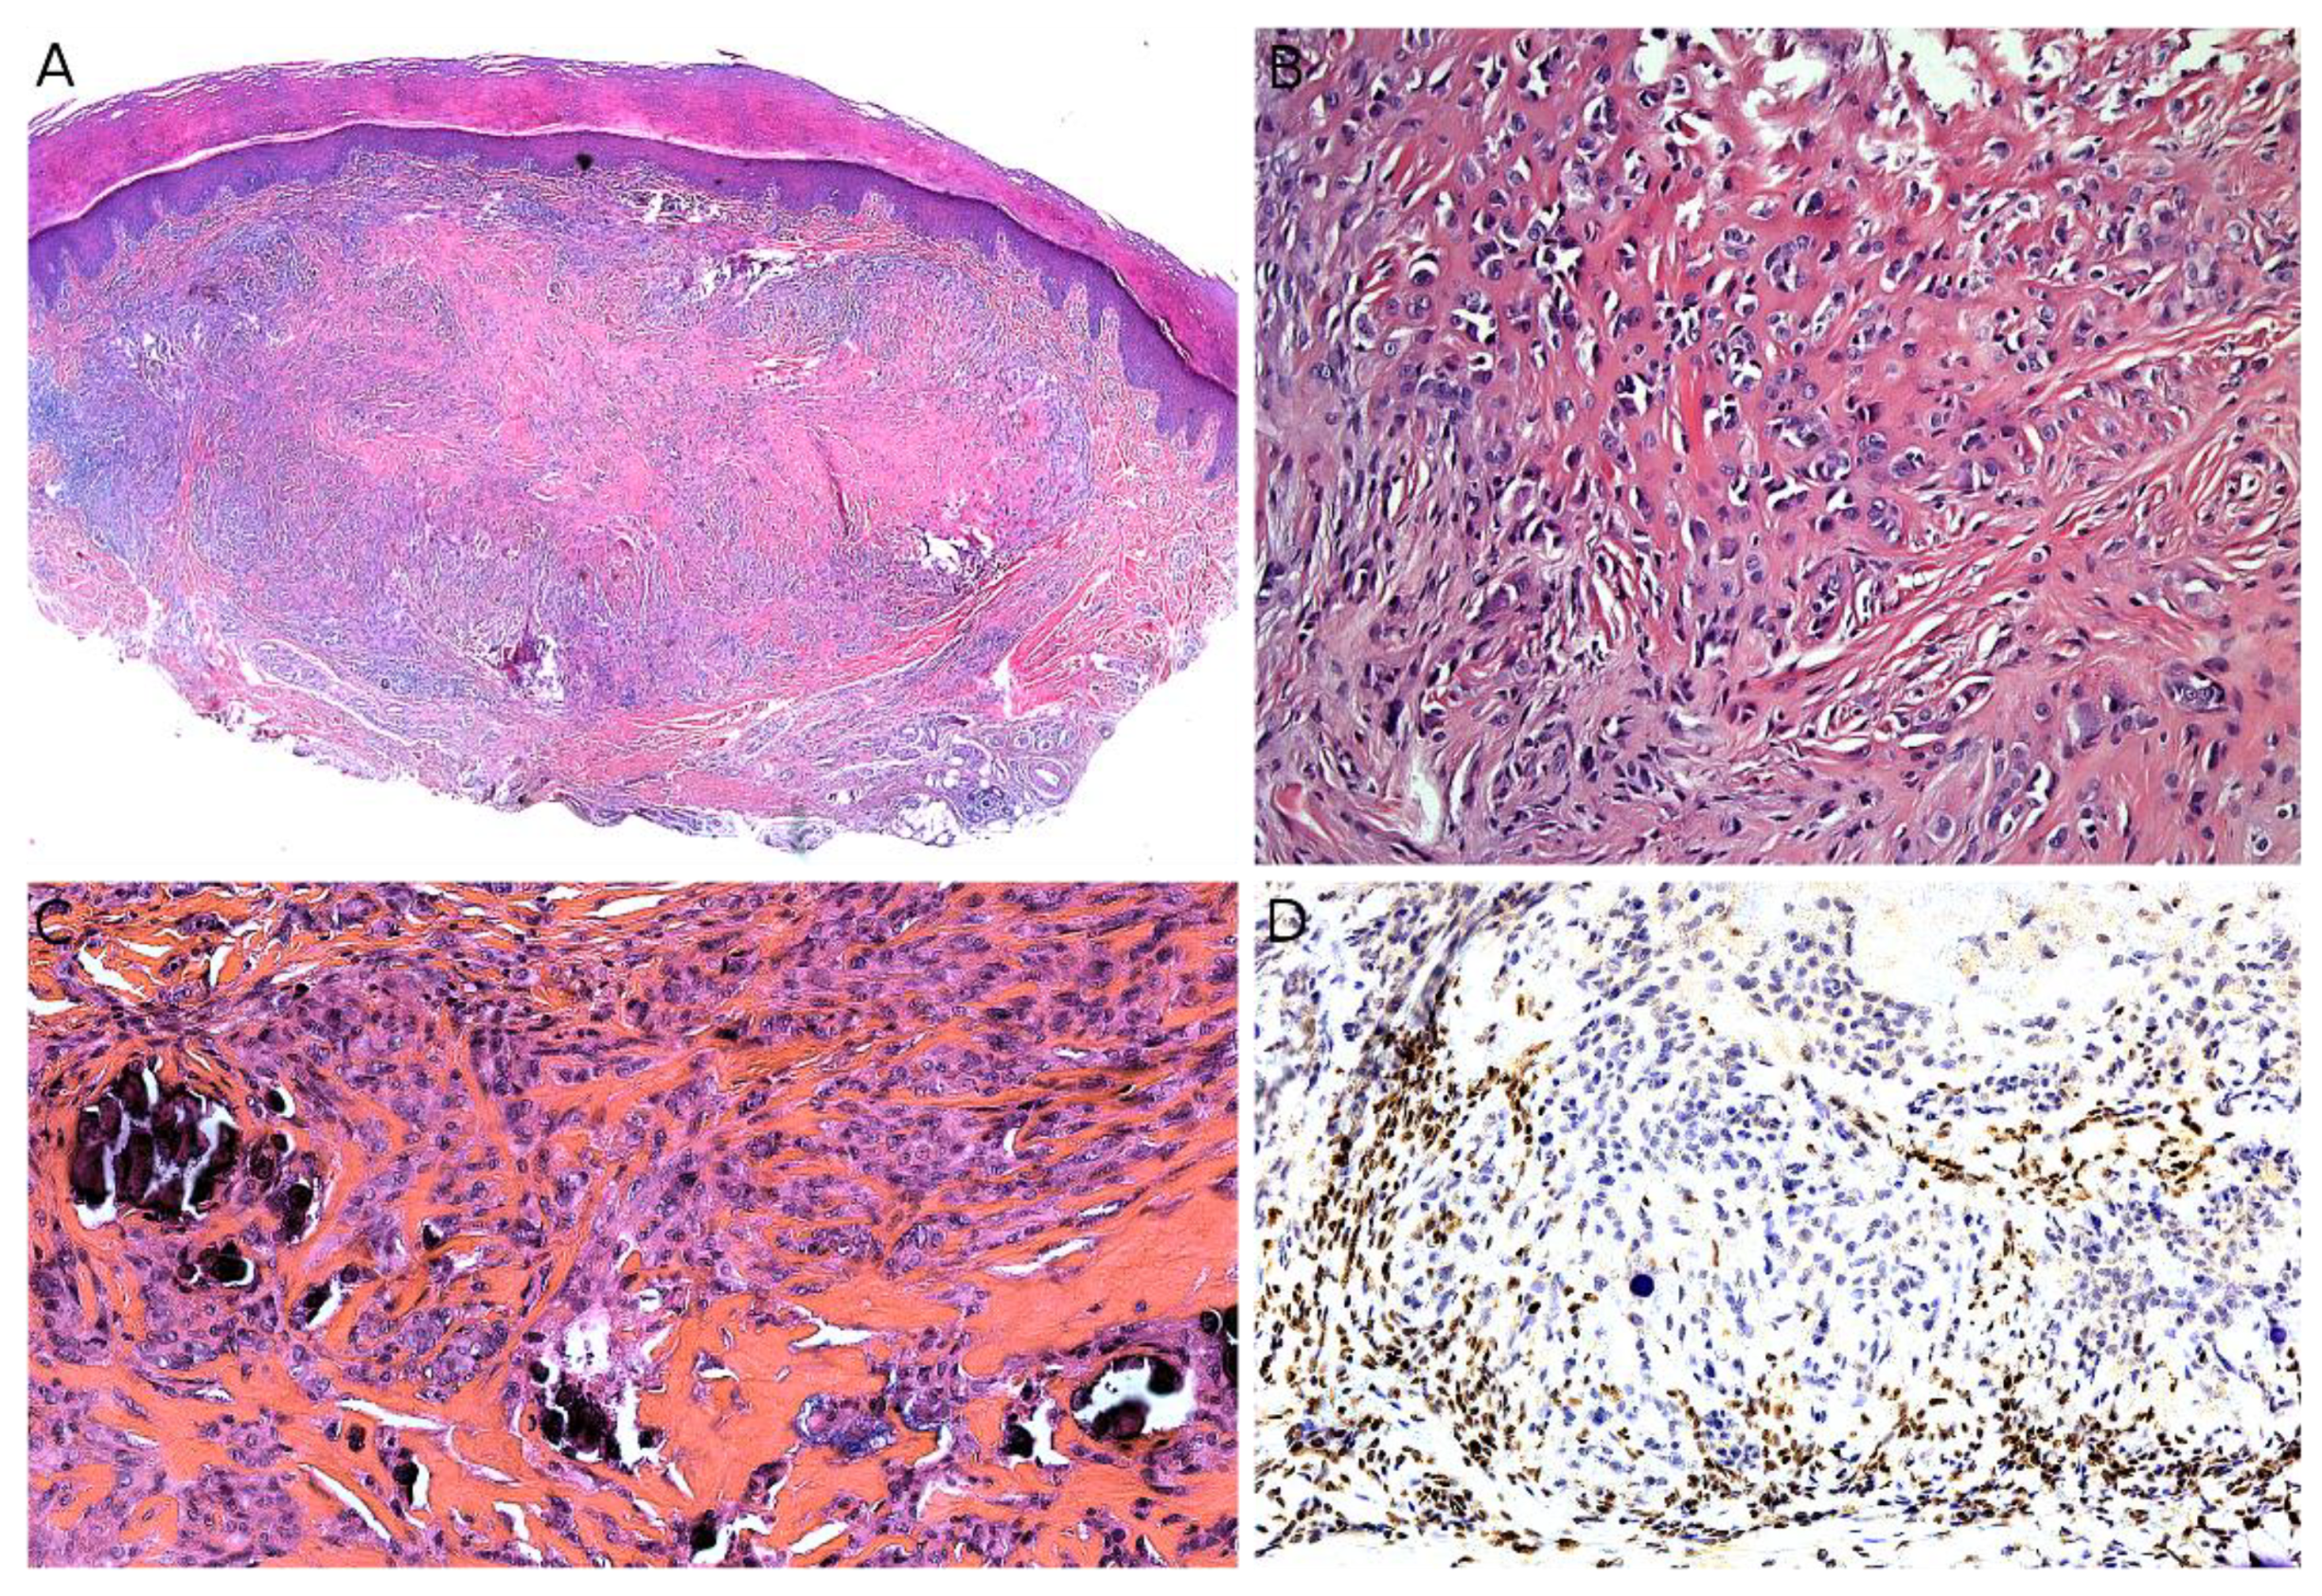

2.6. Dermatofibrosarcoma Protuberans/Giant Cell Fibroblastoma

2.7. Plexiform Fibrohistiocytic Tumor